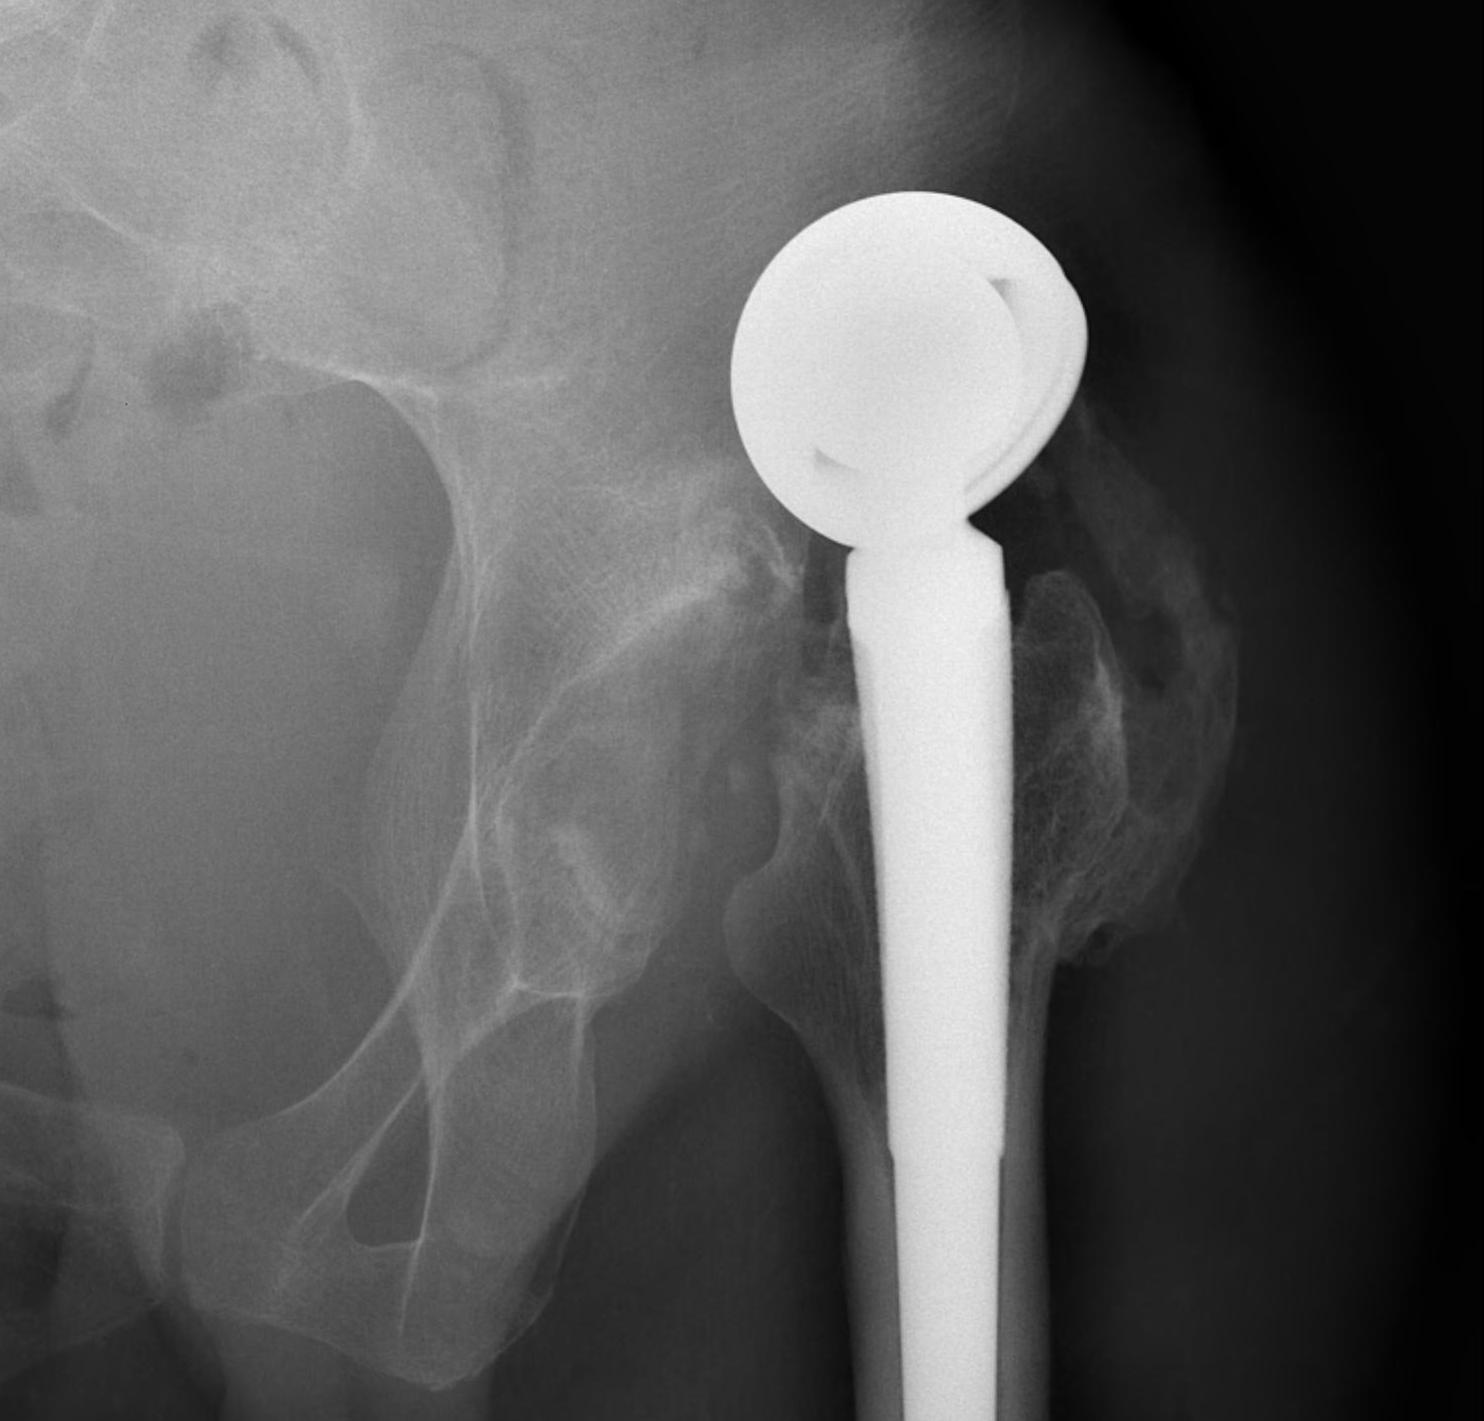

Unipolar

- single articulation between prosthesis and acetabulum

Unipolar monoblock

- Austin Moore press fit

- Thompson cemented

- no offset options

Austin Moore Thompson